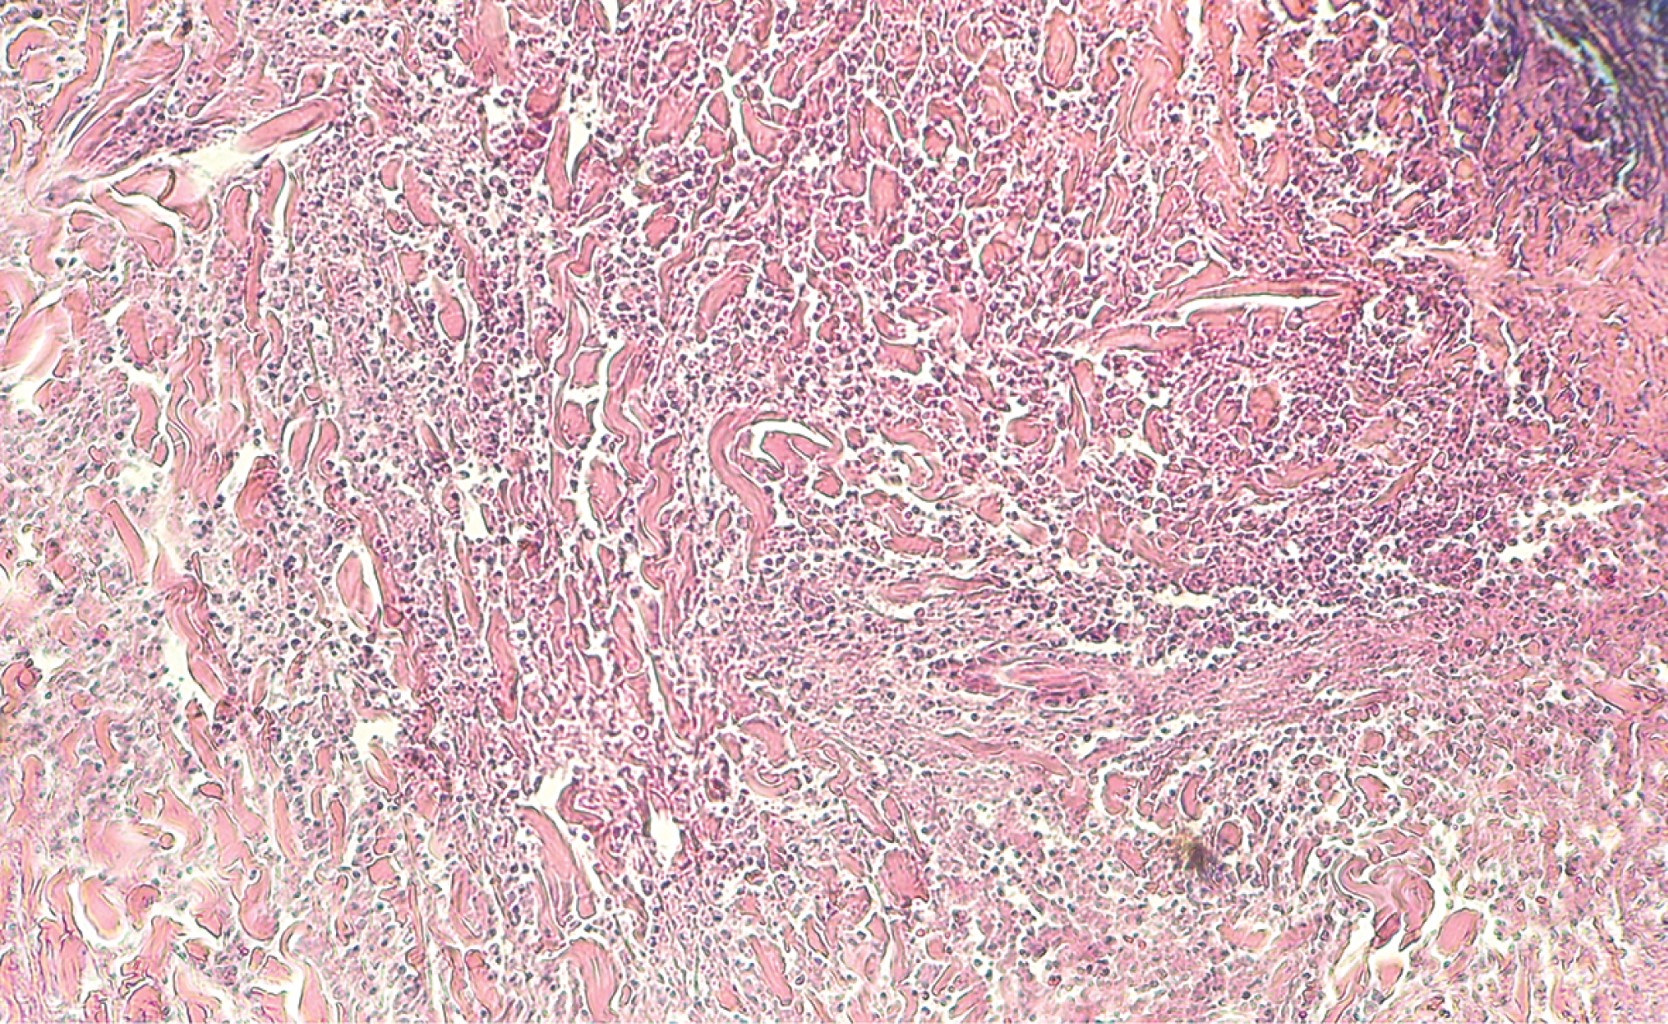

Cutaneous polyarteritis nodosa: presentation of two cases and literature review

Cutaneous polyarteritis nodosa is a form of vasculitis that affects small to medium sized arteries, with unknown incidence due to a low frequency. The exact etiopathogenesis is unknown. Clinically, it is characterized by painful subcutaneous nodules associated to livedo reticularis, that frequently evolves to ulcers on lower extremities, with a chronic and relapsing clinical course. Generally, it only involves skin, however, extracutaneous manifestation has been reported. In this article we describe different clinical presentation and management of two patients with different gender and age.

Figure 2